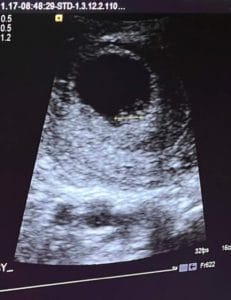

Essure Reversal, Excited To Be A Mom Again

Becoming A Mom Again

I’m very excited to know that I will be a mom again of a beautiful baby.

Patient age: 37

Tubal ligation type: Essure

Patient hometown: Wilmington, Delaware